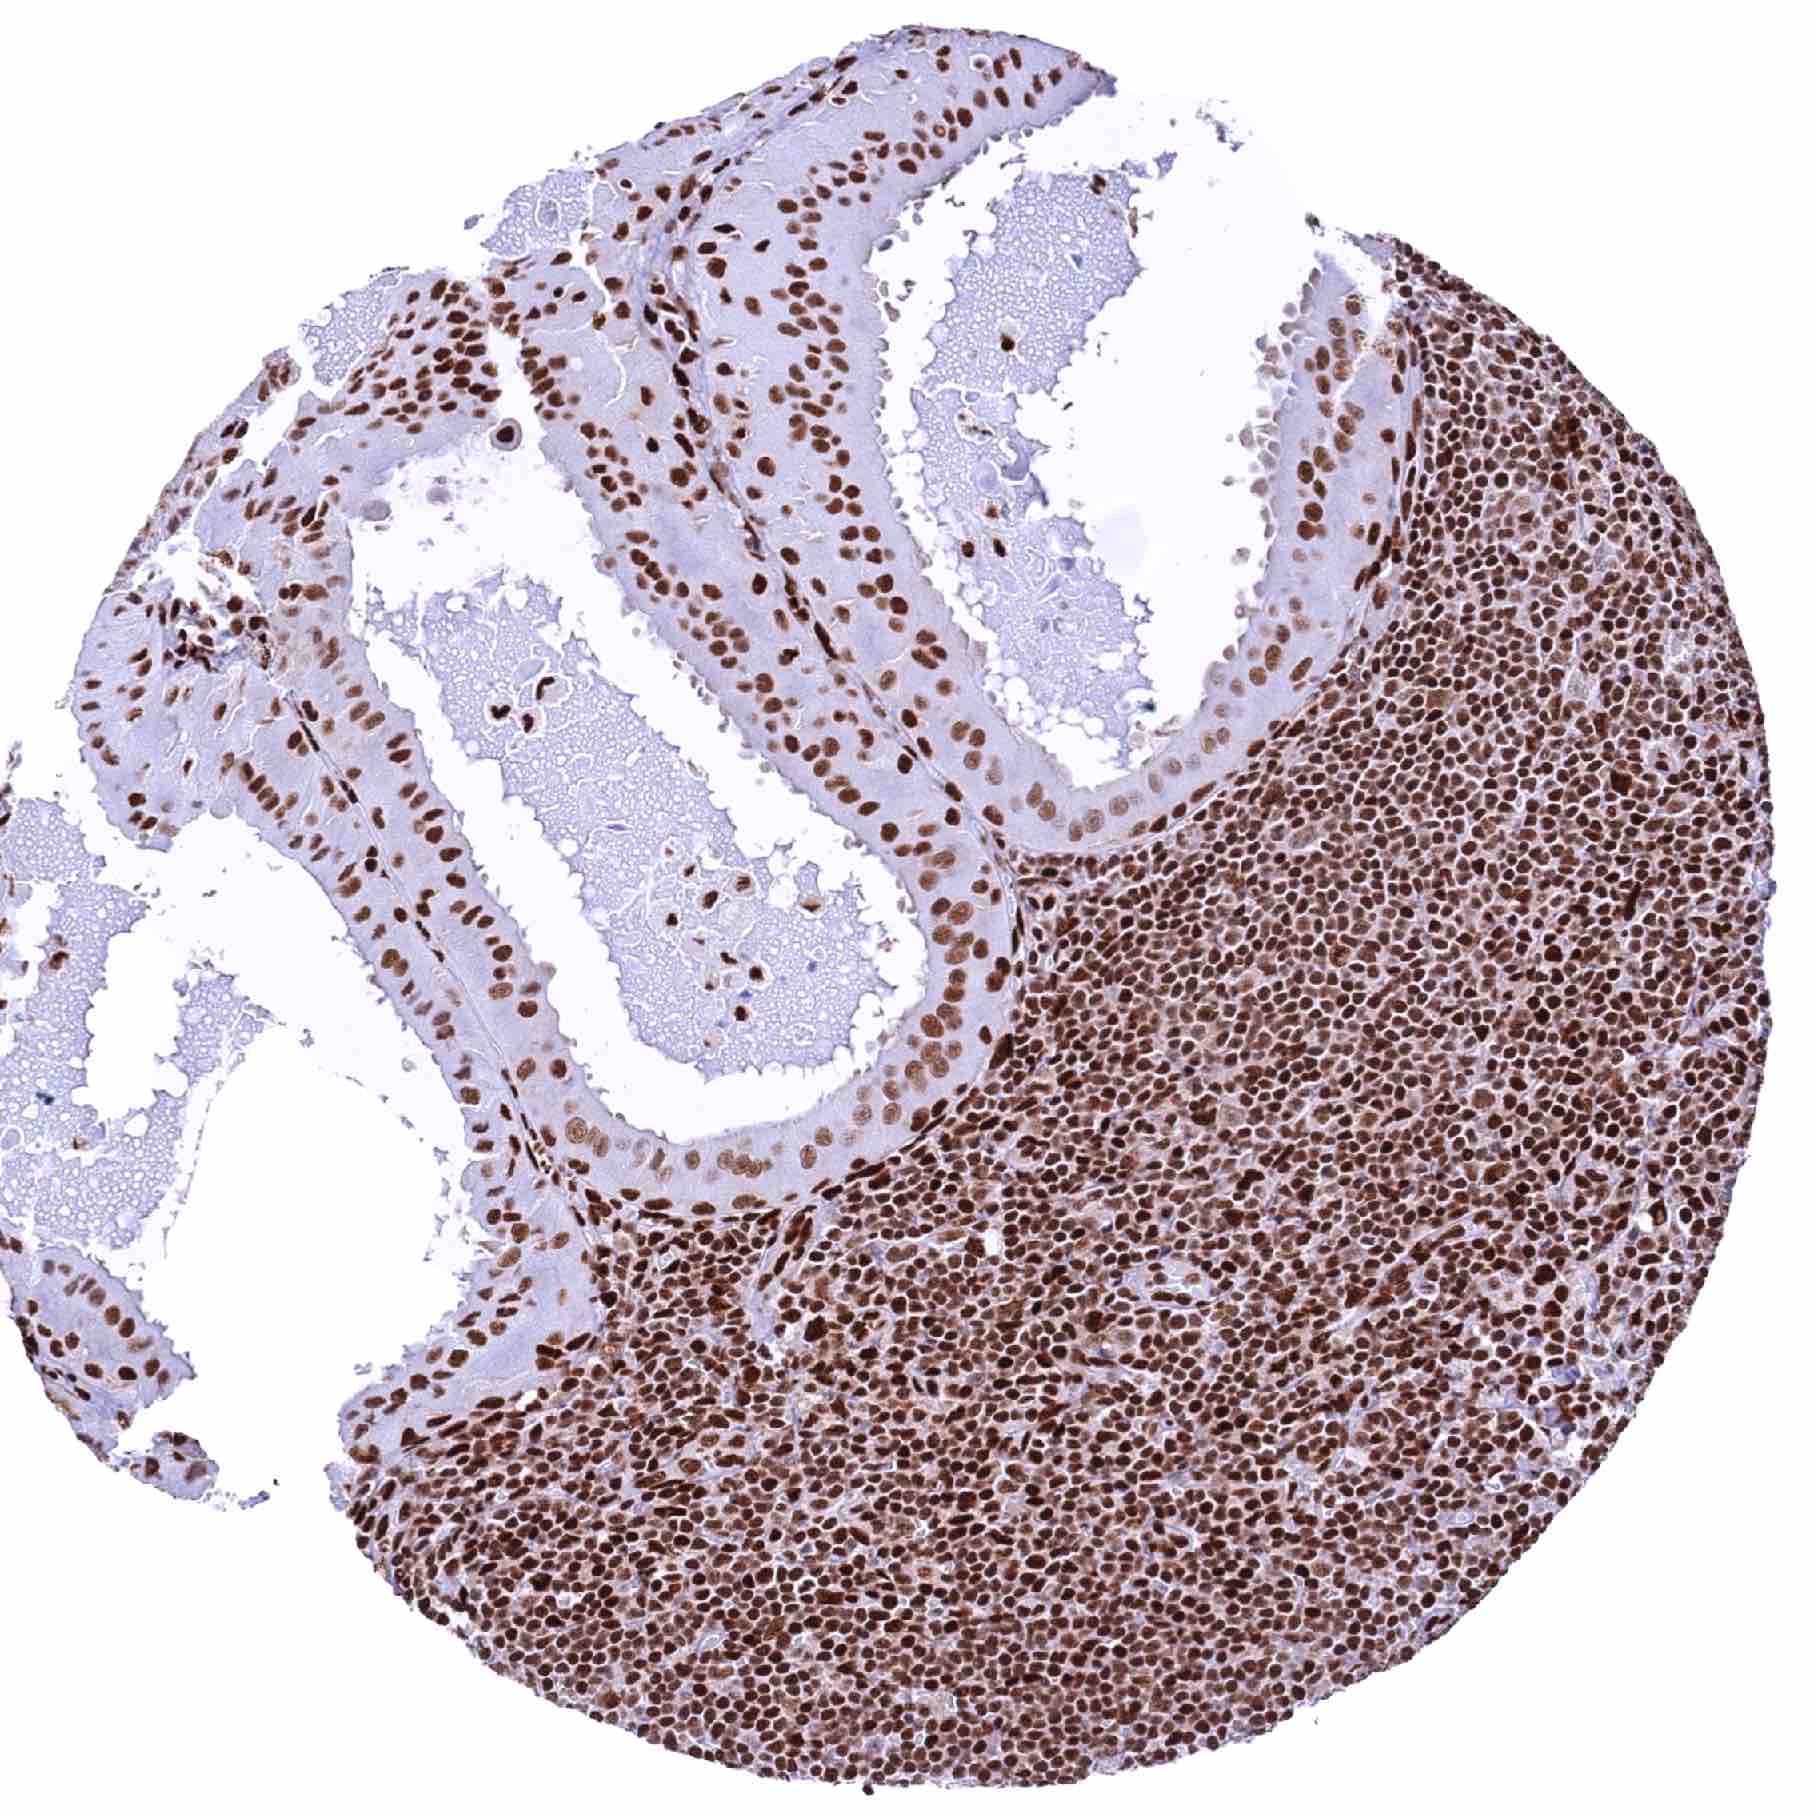

Lymph node – Follicular B-cell lymphoma with strong GR staining of all tumor cells